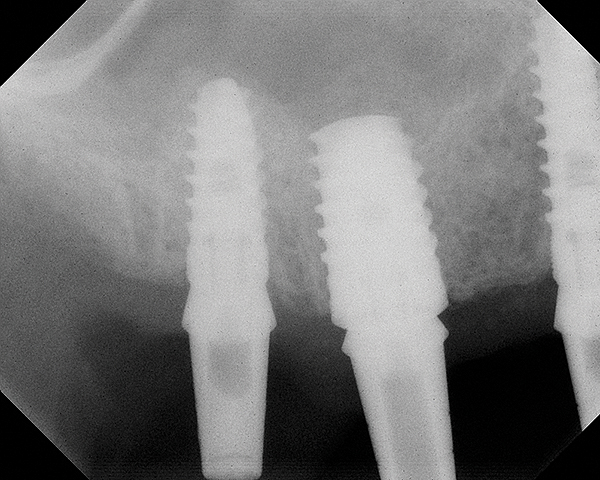

This patient was a 73-year-old man with only about 3.5 mm of native bone in the No. 3 site (Figure 20). The composite graft used here was a 50:50 mixture of DFDBA and deproteinized bovine bone mineral (Osteohealth, www.osteohealth.com) with approximately 40% calcium sulfate added. The implant was the same type and length as in Case 1 above. Figure 21 shows the area on the day of placement. In the CBCT scan on the day of placement (Figure 22), the native bone and bone graft were clearly discernable. However, the postoperative radiograph taken at 6.5 months (Figure 23) showed no marginal bone loss and a significantly denser appearance than when the graft was place. The membrane was raised about 7 mm to 8 mm. The final radiograph was taken after extraction of tooth No. 2 and after extraction of tooth No. 4 and immediate implant placement.

Fig 20. Case 3. Preoperative radiograph showing about 3.5 mm of ridge height.

Figure 20

Fig 21. Day of sinus augmentation and implant placement in the No. 3 position. The sinus membrane has been raised about 7 mm to 8 mm.

Figure 21

Fig 22. CBCT scan (Kodak 9000D) of No. 3 area, day of placement. Appearance of native bone and bone graft is clearly discernible.

Figure 22

Fig 23. 6.5-month postoperative radiograph. Teeth Nos. 2 and 4 have been extracted and an immediate implant had been placed in the No. 4 position.

Figure 23